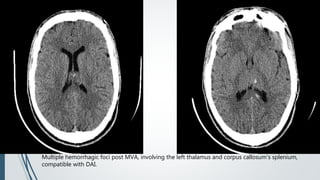

Multiple hemorrhagic foci post MVA, involving the left thalamus and corpus callosum's splenium,

compatible with DAI.